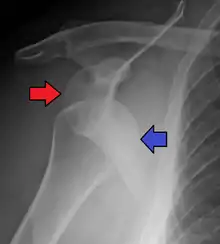

An anterior dislocation of the shoulder

Anterior dislocation of the right shoulder. AP X ray

In over 95% of shoulder dislocations, the humerus is displaced anteriorly.[6] In most of those, the head of the humerus comes to rest under the coracoid process, referred to as sub-coracoid dislocation. Sub-glenoid, subclavicular, and, very rarely, intrathoracic or retroperitoneal dislocations may also occur.[7]

Anterior dislocations are usually caused by a direct blow to, or fall on, an outstretched arm. The person typically holds his/her arm externally rotated and slightly abducted.

A Hill–Sachs lesion is an impaction of the head of the humerus left by the glenoid rim during dislocation.[5] Hill-Sachs deformities occur in 35–40% of anterior dislocations. They can be seen on a front-facing X-ray when the arm is in internal rotation.[8] Bankart lesions are disruptions of the glenoid labrum with or without an avulsion of bone fragment.